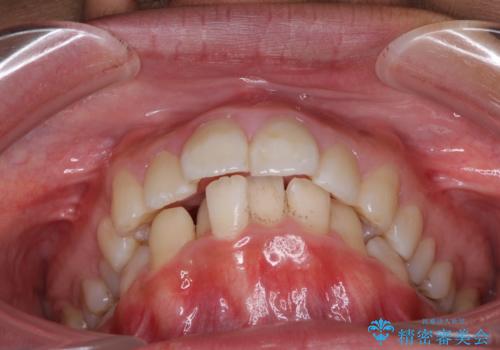

口が閉じられない 抜歯矯正で口元をスッキリと

- 上下の出っ歯を気にして来院された患者様です。

口元を積極的に引っ込めるために、上下左右の第一小臼歯を4本抜歯することとしました。